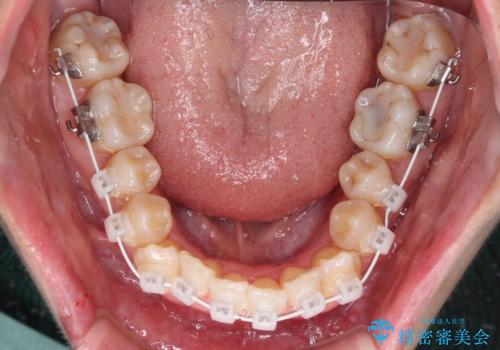

2. 治療途中

2. 【モニター】急速拡大装置 狭い歯列を拡大してワイヤー装置で短期間治療の治療中

2.